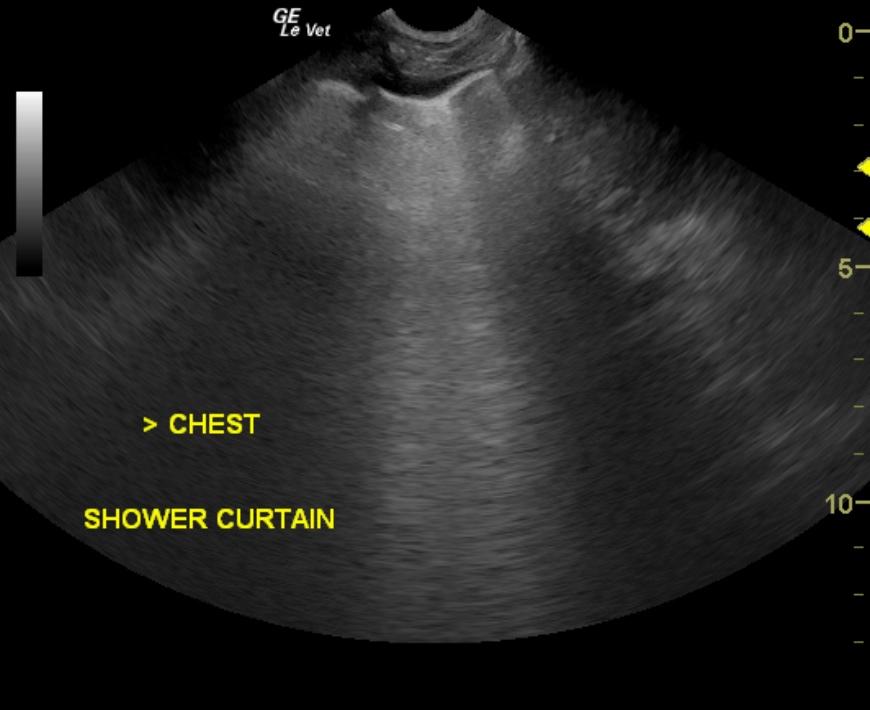

A 3-year-old FS Pitbull Terrier mix was presented for weight loss. The only significant abnormality on physical examination was pale mucous membranes. CBC and blood chemistry showed leukopenia, thrombocytopenia, lymphopenia, hypoproteinemia, hypoalbuminemia, elevated liver enzyme activity, hyperbilirubinemia, hypocalcemia, hypokalemia, hypocholesterolemia, and hyperamylasemia. Lyme, Ehrlichia canis, Rocky Mountain Spotted Fever and leptospirosis results were all negative. Random cortisol was elevated. The patient was being treated with I.V. fluids, Hetastarch, penicillin, and dexamethasone, and then switched to oral prednisone and Clavamox.